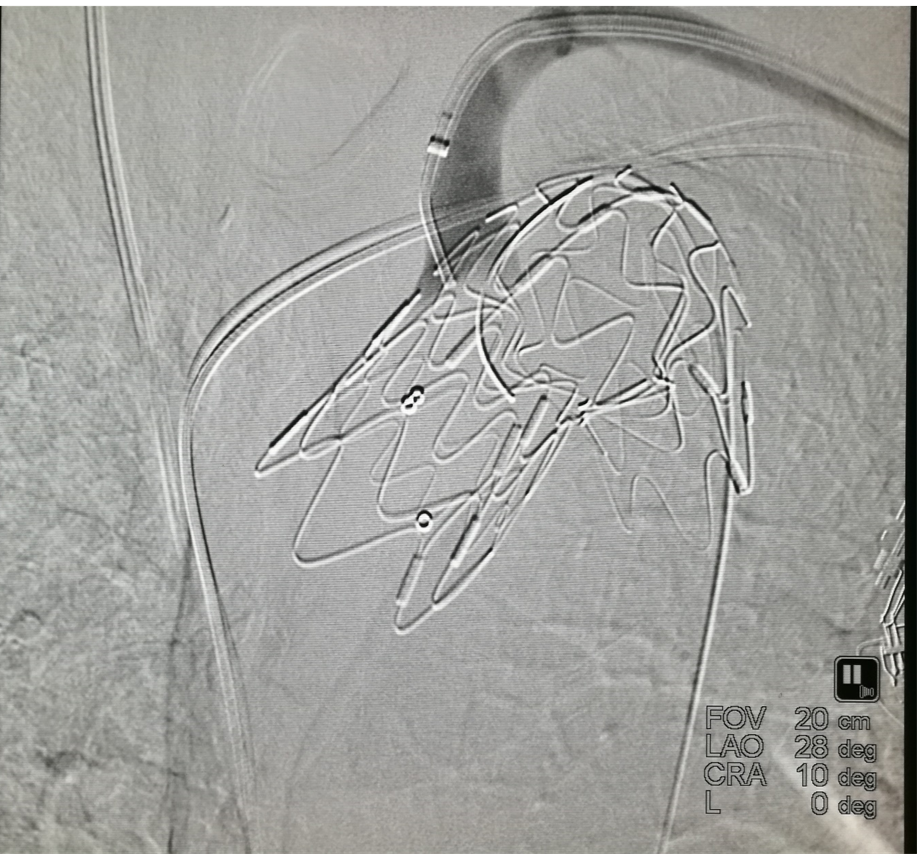

后顶模式:

先释放主体覆膜支架;

将长鞘顶住支架,推送器械使其前盘在主动脉内张开并向后牵拉,同样实现锚定于分支开口;

再行破膜。

输送器顶住覆膜支架,张开后向后牵拉卡住分支开口